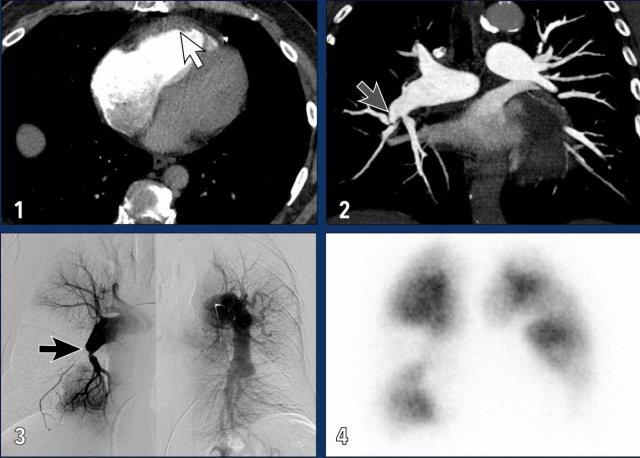

Đặc điểm hình ảnh

Các hình ảnh này thuộc về bệnh nhân bị CTEPH nặng.

- Giãn nhĩ phải và thất phải kèm phì đại cơ thất phải (mũi tên trắng).

- Dải mô (web) gây hẹp động mạch phổi phân thùy; đây là một trong những đặc điểm của bệnh huyết khối tắc mạch mạn tính (mũi tên xám).

- Hình ảnh chụp mạch phổi cho thấy tắc hoàn toàn (mũi tên đen) và hẹp các động mạch phổi phân thùy, kèm theo các khuyết tưới máu lớn.

- Các khuyết tưới máu hình chêm trên xạ hình tưới máu.

Phì đại động mạch phế quản trong CTEPH

Giãn động mạch phế quản gợi ý thêm về các bất thường lâu dài trong lưu lượng máu động mạch phổi, với sự huy động tuần hoàn động mạch hệ thống như một nguồn tưới máu phổi thay thế.

Hình ảnh

Giãn các động mạch phế quản (mũi tên) ở bệnh nhân tăng áp động mạch phổi.

Lưu ý các động mạch phổi giãn rộng.